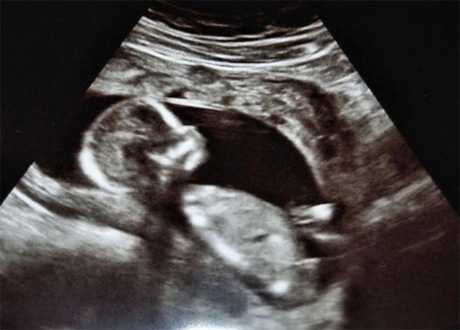

Generalmente cuando se comienza un embarazo el médico corrobora el mismo mediante una ecografía en 2D en la cual se puede apreciar, la longitud y parte de su crecimiento por medio de imágenes planas en blanco y negro. Esta ecografía es la más tradicional de todas, y permite diagnosticar alteraciones cromosómicas, malformaciones genitourinarias, y el desarrollo del sistema cardiovascular.